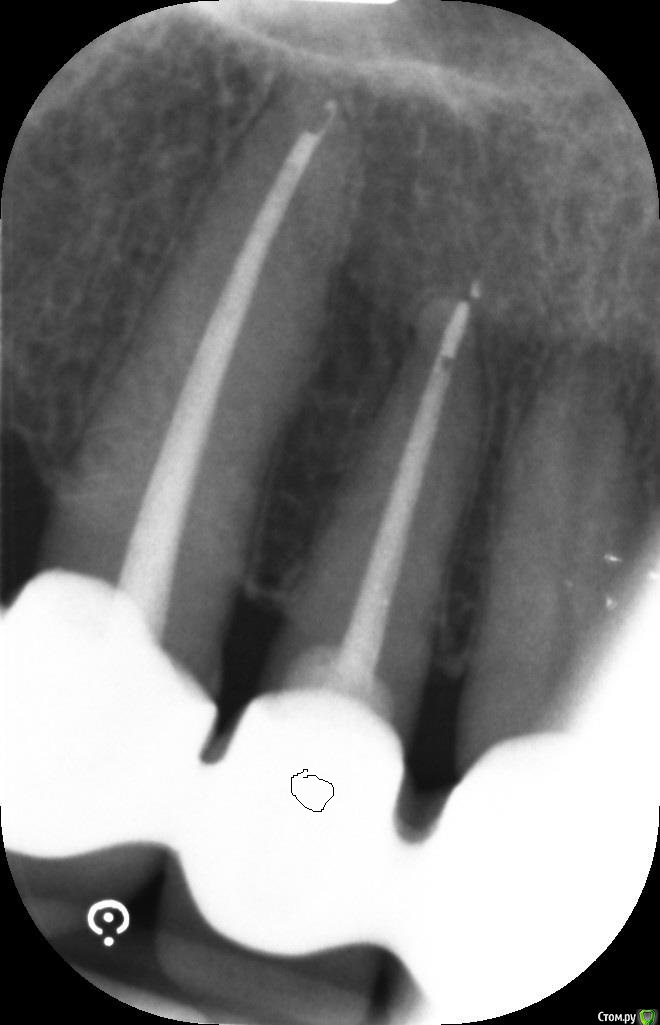

ellenchik Опубликовано 9 января, 2020 Автор Поделиться Опубликовано 9 января, 2020 Добрый день, уважаемые Доктора.Я снова к Вам за советом. После отпуска ( Перемена климата -прилетела из +25 в +2 град.) уже неделю болит уже другой передний зуб под коронкой (канал пролечен 4,5 г. назад) Болит очень высоко с внешней стороны десны в самом вверху. Особенно при нажатии точки прямо под правой ноздрёй носа. Боль жгучая,ноющая. С нёбной стороны никаких болевых ощущений. Временами такая "гуляющая" боль по передним верхним зубам. Врач сделал снимки и сказал, что надо делать резекцию верхушки корня у этого зуба и заодно у рядом стоящего зуба (по моему клык) с пролеченным каналом. Еще он где-то увидел трещину.В рот заглянул,но зубы ни на какие реакции не проверял. На снимках причинный зуб (по моим ощущениям ) с "кривым кружочком"Буду очень признательна за советы. Действительно все так плохо по снимкам и необходима резекция обоих зубов? Или есть другие варианты. И на каком зубе видна трещина? С уважанием ЕленаP.S-Прикрепляю на всякий случай старый снимок ( третий по счету ) этих зубов после лечения в 2015 г. Ссылка на комментарий

ellenchik Опубликовано 10 января, 2020 Автор Поделиться Опубликовано 10 января, 2020 Посмотрите ,пожалуйста снимки. Что можно по ним сказать?К кому лучше с этим обратиться, к хирургу или эндодонтисту?У меня еще и в понедельник 13.01 запланирована небольшая операция,отменить нельзя. (не с зубами связано) 1)Можно ли отложить лечение зуба на неделю?2). может пока Антибиотики? С уважением Елена Ссылка на комментарий

ellenchik Опубликовано 12 января, 2020 Автор Поделиться Опубликовано 12 января, 2020 Посмотрите ,пожалуйста снимки. Что можно по ним сказать?К кому лучше с этим обратиться, к хирургу или эндодонтисту?У меня еще и в понедельник 13.01 запланирована небольшая операция,отменить нельзя. (не с зубами связано) 1)Можно ли отложить лечение зуба на неделю?2). может пока Антибиотики? С уважением Елена Ссылка на комментарий

ellenchik Опубликовано 12 января, 2020 Автор Поделиться Опубликовано 12 января, 2020 Если мои снимки малоинформативны,подскажите плиииз... Сделаю новые.Но всё же надеюсь Ваши мнения по поводу резекции корней. Очень нужен компетентный взгляд со стороны. Может есть другие варианты и не так всё критично по снимку. Буду очень признательна. Ссылка на комментарий